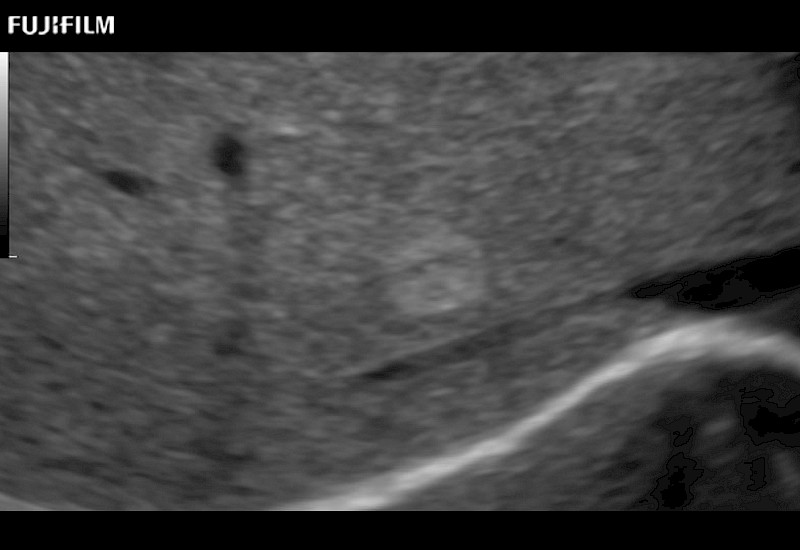

Our dedication to Surgical Oncology allows us to offer superior image quality, outstanding system reliability and intuitive use of cutting edge technology.